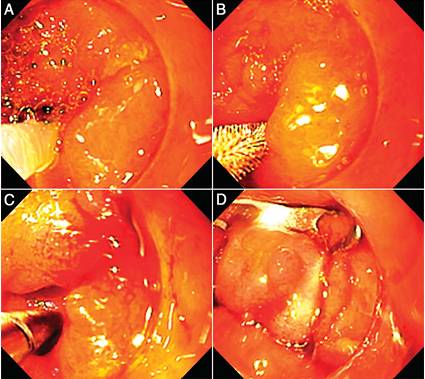

针刀治疗也可用于肛直肠吻合和储袋-肛管吻合口的窦道,治疗前也需要常规行多普勒超声探查切开的窦道壁局部无血管结构,用ERCP电切模式切开窦道和储袋的共同壁,再以金属夹沿切缘夹闭切开的窦道防止肠壁间的再通(图11)。局部喷洒双氧水以清洁窦腔,最后,窦腔内喷洒强力霉素(100mg静脉用粉剂,用10 ml生理盐水稀释)或50%葡萄糖10 ml以促进肉芽增生和纤维化。

图11. 内镜针刀窦切开术。 (A) 吻合口窦道 (绿色箭头) (B) 以针刀切开。 (C) 金属夹沿切缘夹闭切开的窦道。 (D)管腔上皮化使窦道转化为憩室(绿色箭头)。